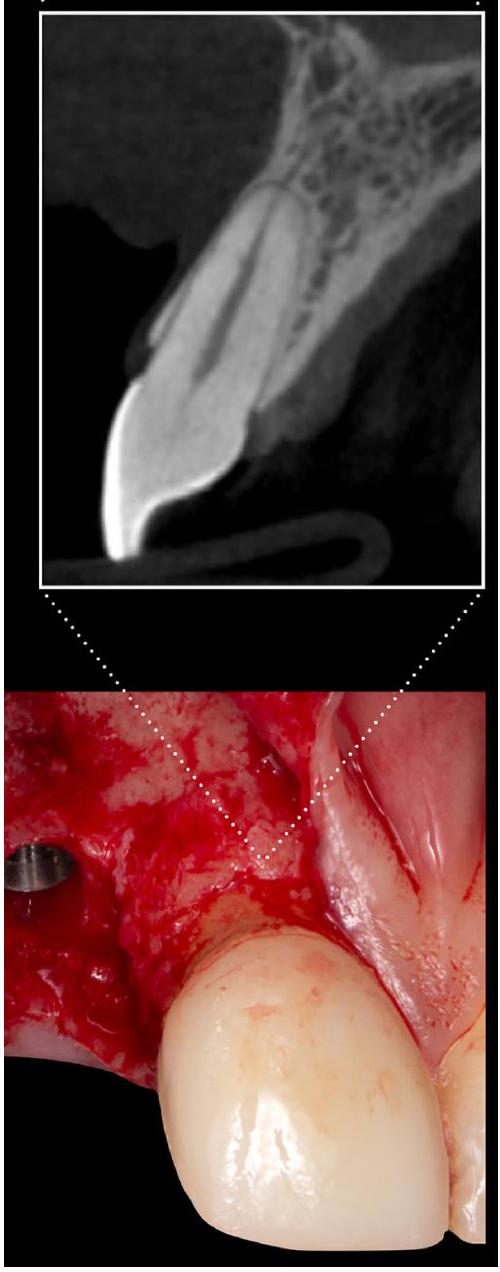

- أثناء المسح، يجب فصل الأنسجة الرخوة الوجهية (الشفاه) عن قمة الحويصلات، على سبيل المثال، بواسطة لفة قطنية موضوعة في الفم لزيادة التباين المحلي.

teeth, such as the use of merely visual inspection of the external features of the alveolar ridge and soft tissues,

2.2.2 | Anatomical factors

- During the scan, facial soft tissue (lip) should be separated from the alveolar crest, for example, by a cotton roll placed in the vestibulum to increase local contrast.

or the supracrestal tissue dimensions, the combination of a CBCT with an optical surface scan can provide more accurate results.